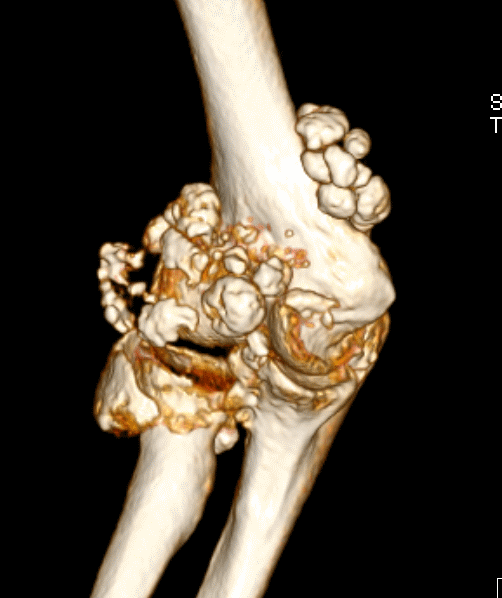

肘关节滑膜软骨瘤病

肘关节镜治疗滑膜软骨瘤病